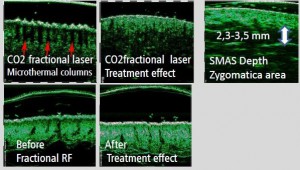

-Μέθοδοι θεραπείας υψηλής ενέργειας

(λέιζερ, RF-Ραδιοσυχνότητα, HIFU-Υψηλής Έντασης Εστιασμένος Υπέρηχος, κ.λπ.)